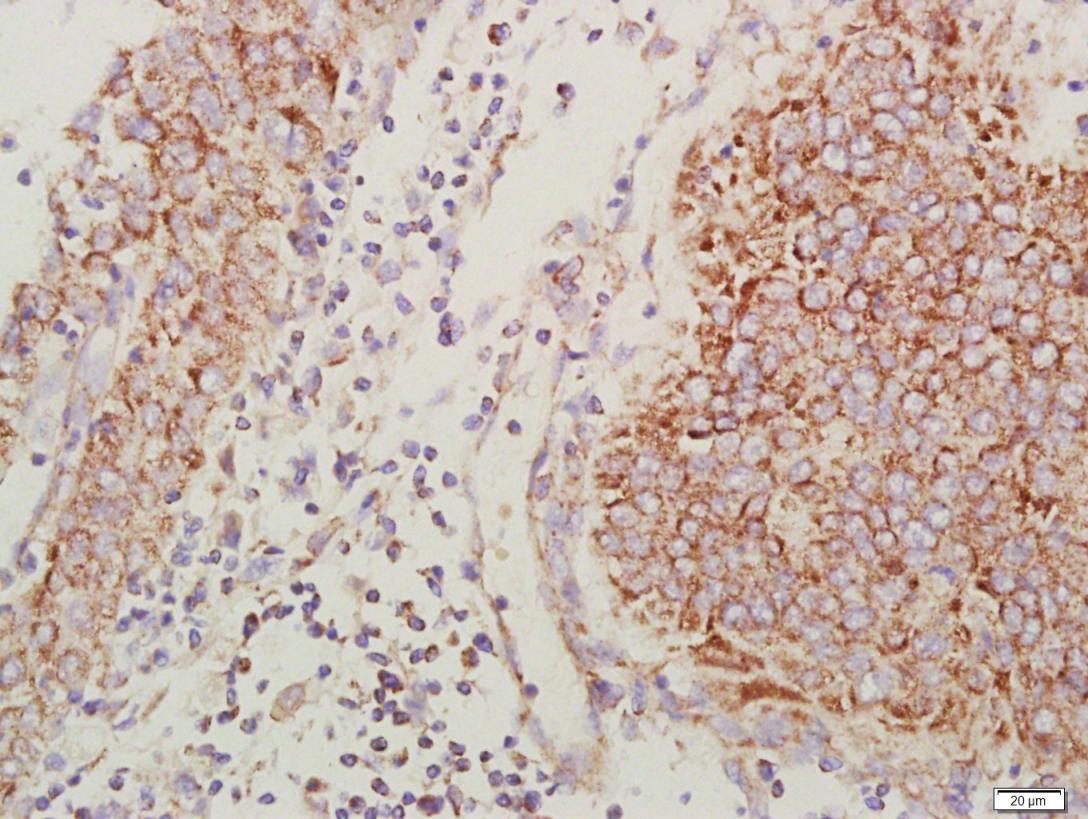

| IHC-P | Human, Mouse, Rat | 1:100-500 | |